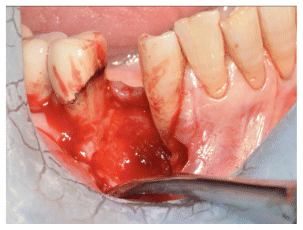

- Epithelial Healing:

Complete epithelialization was observed in 14 out of 15 patients within a median of 3 PRF applications (range: 2–8). In most cases, the first clinical signs of granulation tissue and epithelial closure appeared as early as the second visit. (Figure 2-3-4) - Pain Reduction: